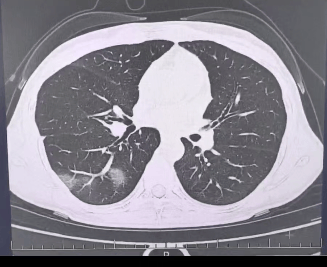

检查结果显示如何进入币圈,

程女士的好几叶肺

都出现了“白肺”现象如何进入币圈,

指间血氧饱和度只有 88%如何进入币圈,

血心肌酶谱、肌钙蛋白的指标、肝功能的指标

也出现了明显的异常如何进入币圈。

确诊流感(重型)如何进入币圈!

图源:杭州市第三人民医院微信公众号